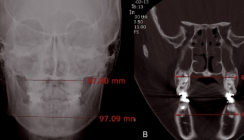

Aber auch von außen auf das Gewebe einwirkende Kräfte, wie die Zunge oder sogar auch die, wenn auch mit geringen Kräften, aber dennoch permanent durch die Nasenhöhle strömende Atemluft, wirken formgestaltend. Auf dieser Erkenntnis basiert die Funktionskieferorthopädie als therapeutisches Prinzip. Wenn ein Kreuzbiss vorliegt, der auf ein Wachstumsdefizit der Maxilla zurückzuführen ist, kann er auch selbst das weitere Wachstum der Maxilla blockieren (Abb. 9a). Zur Therapie ist es dann fol­gerichtig, jeglichen Druck von vestibulär auf den Alveolar­fortsatzknochen fortzunehmen und den Druck von palatinal zuzulassen.

Auf dieser verblüffend einfachen, aber biologisch wohl fundierten Erkenntnis beruht das Wirkungsprinzip des Funktionsreglers nach Rolf Fränkel (Abb. 9b, c). Voraussetzung ist, dass auch der Biss gesperrt wird, damit der Kreuzbiss überstellt werden kann und dass der Patient das Gerät gut trägt (Abb. 9d).

Auch wenn der günstige Behandlungszeitpunkt verpasst worden ist, das Wachstum der Maxilla oder zumindest ihres Alveolarfortsatzes (Processus alveolaris maxillae) noch im frühen Wechselgebiss ausreichend zu fördern (Abb. 9a–d), besteht durchaus noch die Möglichkeit des dentoalveolären Ausgleichs im bleibenden Gebiss eines jungen jugendlichen Patienten. Hier ist allerdings das Vorliegen einer maxillären Hypolasie differenzialdiagnostisch abzugrenzen. Im vorliegenden Fall konnte durch Anwendung einer Multibandapparatur und durch den Einsatz einer intensiv getragenen Delaire Maske (Abb. 10a) eine sehr ungünstige frontale Kopfbissverzahnung (Abb. 10b) mit einer dental mesialen Seitenverzahnung (Abb. 10d) noch korrigiert werden (Abb. 10c, e). Bei diesem dentoalveolären Ausgleich handelt es sich in den meisten Fällen allerdings um einen eher kompensatorischen Achsausgleich der Zahnstellung. Beim nachgewiesenen Vorliegen eines basalknöchernen Defizits der Maxilla sollte bei Patienten im späten Wechselgebiss dann eher an eine Erweiterung der Gaumennaht, vorzugsweise mit intraossär verankerten Geräten, gedacht werden. Die Möglichkeit, nach Abschluss des Wachstums ein Größendefizit der Maxilla durch chirurgische Verfahren wie Osteotomien oder Distraktionstechniken, auszugleichen, bleibt je nach Ausgangslage dabei immer noch eine verlässliche Option.